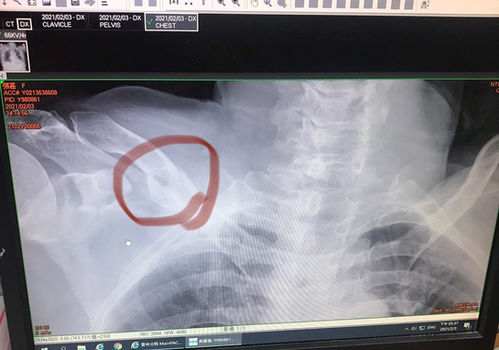

2021年2月3日農曆春節前,媽媽騎著機車從田裡工作要回家,在鄉道路上被一台轎車撞到發生了車禍,送到醫院的時候人已昏迷腦內出血、胸鎖骨粉碎性骨折、右側有嚴重的外傷和骨裂,人躺在加護病房生命危險。

在昏迷不醒中仍狂吐、腹脹,護士很小心的照顧,因為怕媽媽嗆到會有危險,也提醒我們要利用親情呼喚讓媽媽清醒,頭重創蜘蛛網膜出血和嚴重的骨折都需要開刀處理,但因為沒清醒危險性很高,因為疫情的關係每天只開放一次探視30分鐘,我們盡力和媽媽說話,希望她能醒來,但已經過了2天,仍是不見甦醒。